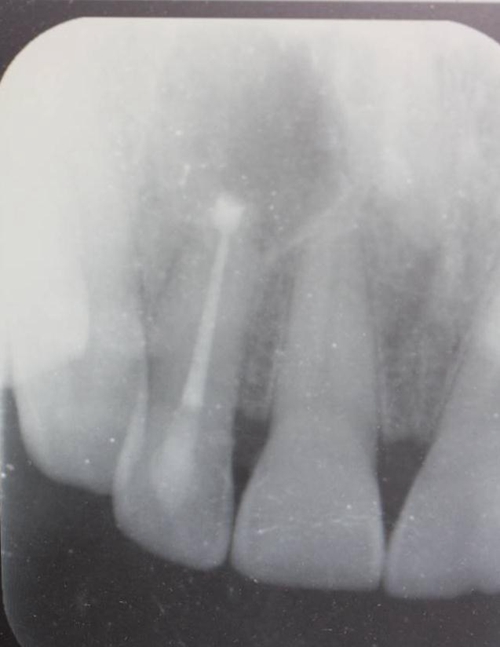

圖1.患者在根管術(shù)前的根尖片影像檢查:12有開髓孔,根尖有橢圓形陰影。

患者、張xx、前牙唇側(cè)牙齦反復溢膿數(shù)年?,F(xiàn)病史:患者數(shù)年前、無誘因發(fā)現(xiàn)前牙牙齦腫痛溢膿,曾在當?shù)鼐驮\,治療經(jīng)過不詳,治療效果不佳,唇側(cè)溢膿現(xiàn)象為消除,遂來我院就診。??茩z查:21舌側(cè)有開髓孔、根管開放,牙冠成灰褐色。唇側(cè)粘膜有一膿瘺。捫診溢膿。12無松動。x光檢查:12根尖區(qū)橢圓形陰影,界限清楚。診斷:12根尖周炎伴發(fā)根尖囊腫。治療:12行根管治療。一個月后。唇側(cè)膿瘺未消失。建議根管外科手術(shù),患者同意手術(shù)。簽手術(shù)知情同意書。